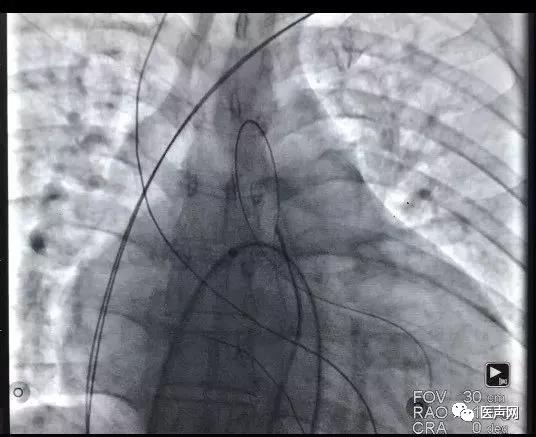

沿导丝送入可撕开长鞘至左室,送入导线(2088TC 65cm)至三维标测指定的靶向位点,经测试,阈值0.5V,螺旋固定。

常规植入右房右室导线,连接机器,手术结束。

最终确认参数,AV间期190ms,VV间期为左右室同时,QRS时限为110ms。